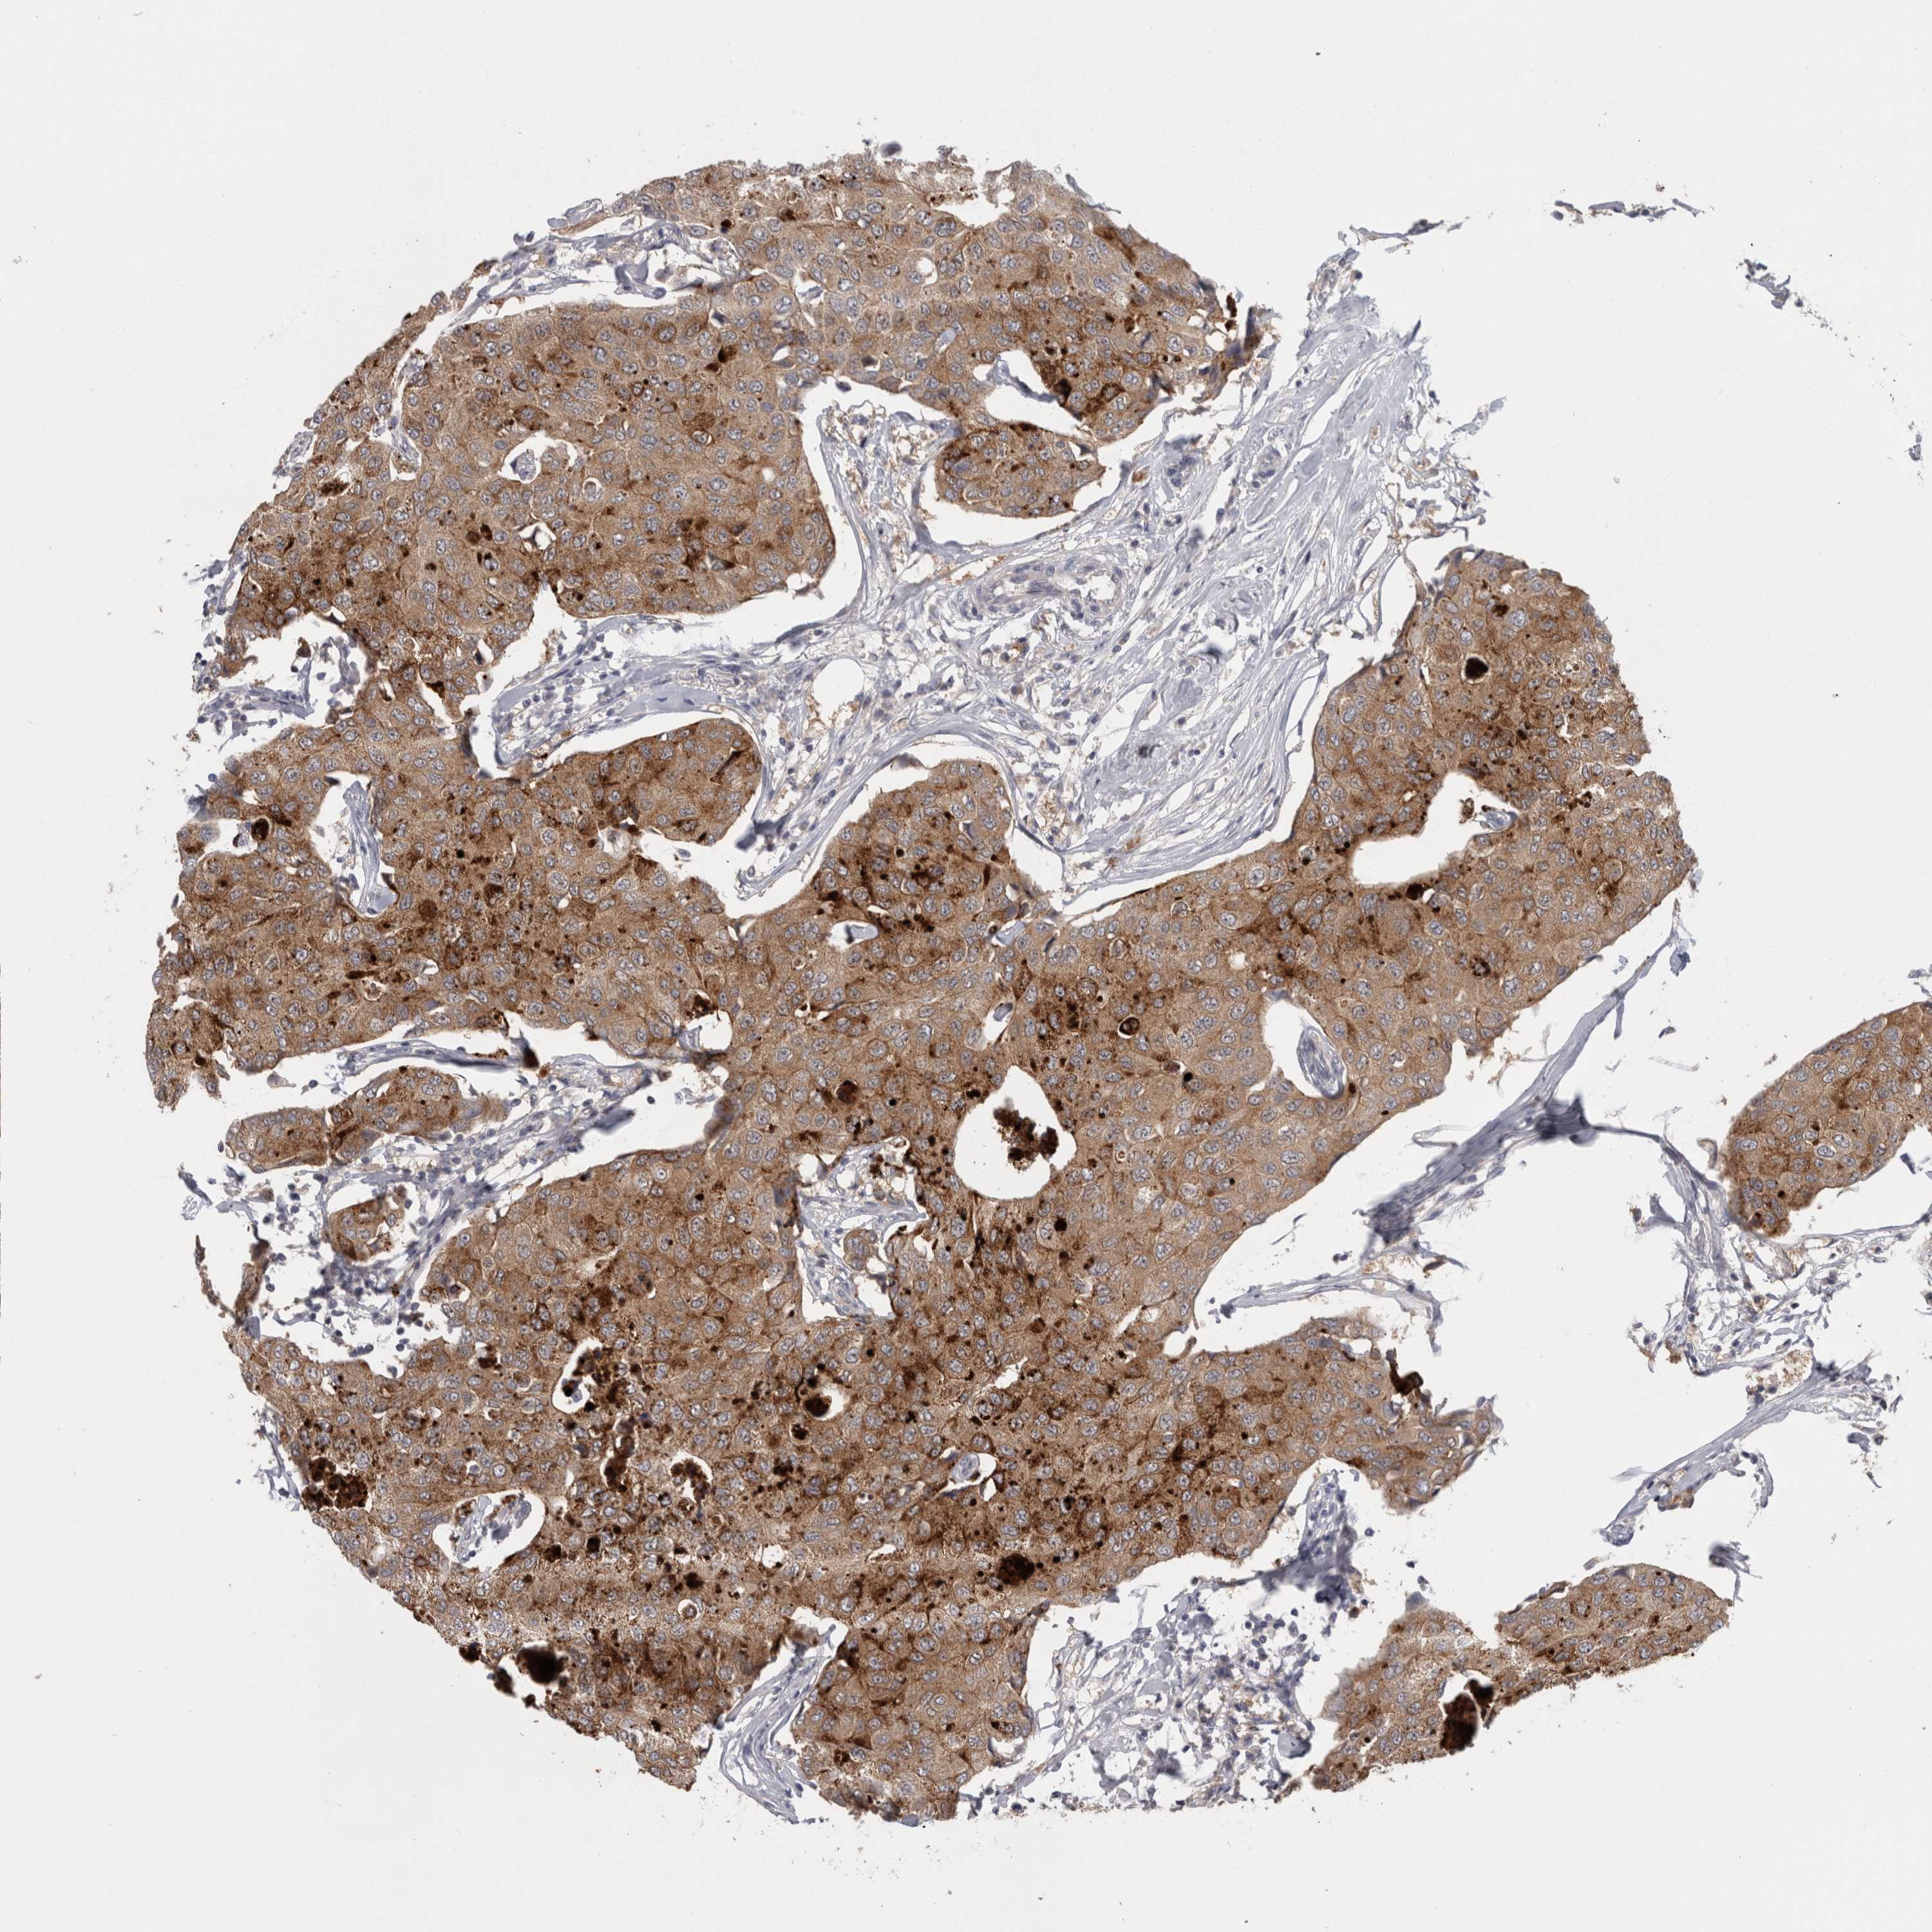

CANCER BREAST CANCER Show tissue menu

BRCA TCGA BRCA VALIDATION PROTEIN EXPRESSION